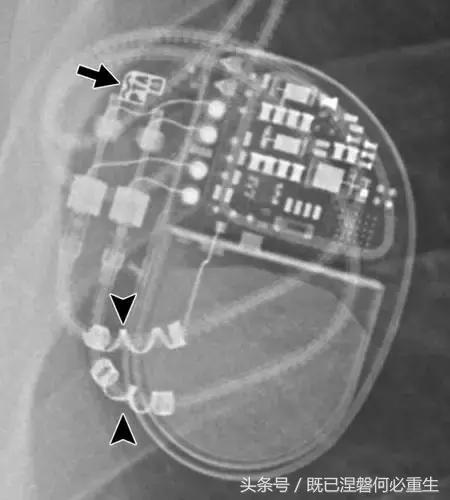

用于将导线的近端部分固定到胸壁的导线固定件可以模拟损伤。扎带是通常位于锁骨和发生器之间并且可以压接引线的套囊(图8A和8B)。熟悉这种外观和通常的射线透射束缚的位置可以防止错误报告磨损的线索。

图。 8A在两个不同患者中电极断裂的电极结合物的实例。

图。 8B在两个不同患者中电极断裂的电极结合物的实例。